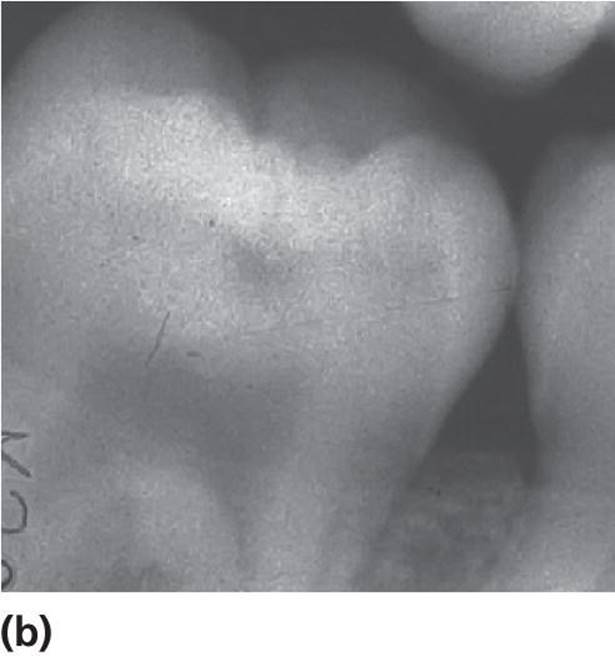

· Active lesions are most frequently seen in erupting and newly erupted teeth in children with other signs of caries activity in the dentition. The discoloration is usually opaque, whitish, or light brownish. Softened enamel at the entrance of the fissure from gentle tactile probing is indicative of an active lesion. When the discoloration also involves obvious loss of continuity of the enamel surface (clinical cavity), bitewing examination frequently reveals a radiolucency in the dentin (Figure 12.5). Many borderline cases can be difficult to diagnose. For these cases, bitewing radiography is a valuable tool for assessing possible dentin involvement (Figure 12.6a,b).

Figure 12.6 (a) Light brown discolored fissures in a permanent first molar of an 8‐year‐old. The enamel around the central fossa is whitish and there is softened enamel at the entrance of the fissure indicating an active lesion (arrow). (b) The radiograph reveals radiolucency in the dentin (arrow). (c) Dark brown/black discolored fissures in a permanent first molar of a 19‐year‐old with a low caries activity. The fissures are hard on probing indicating an arrested (inactive) lesion.